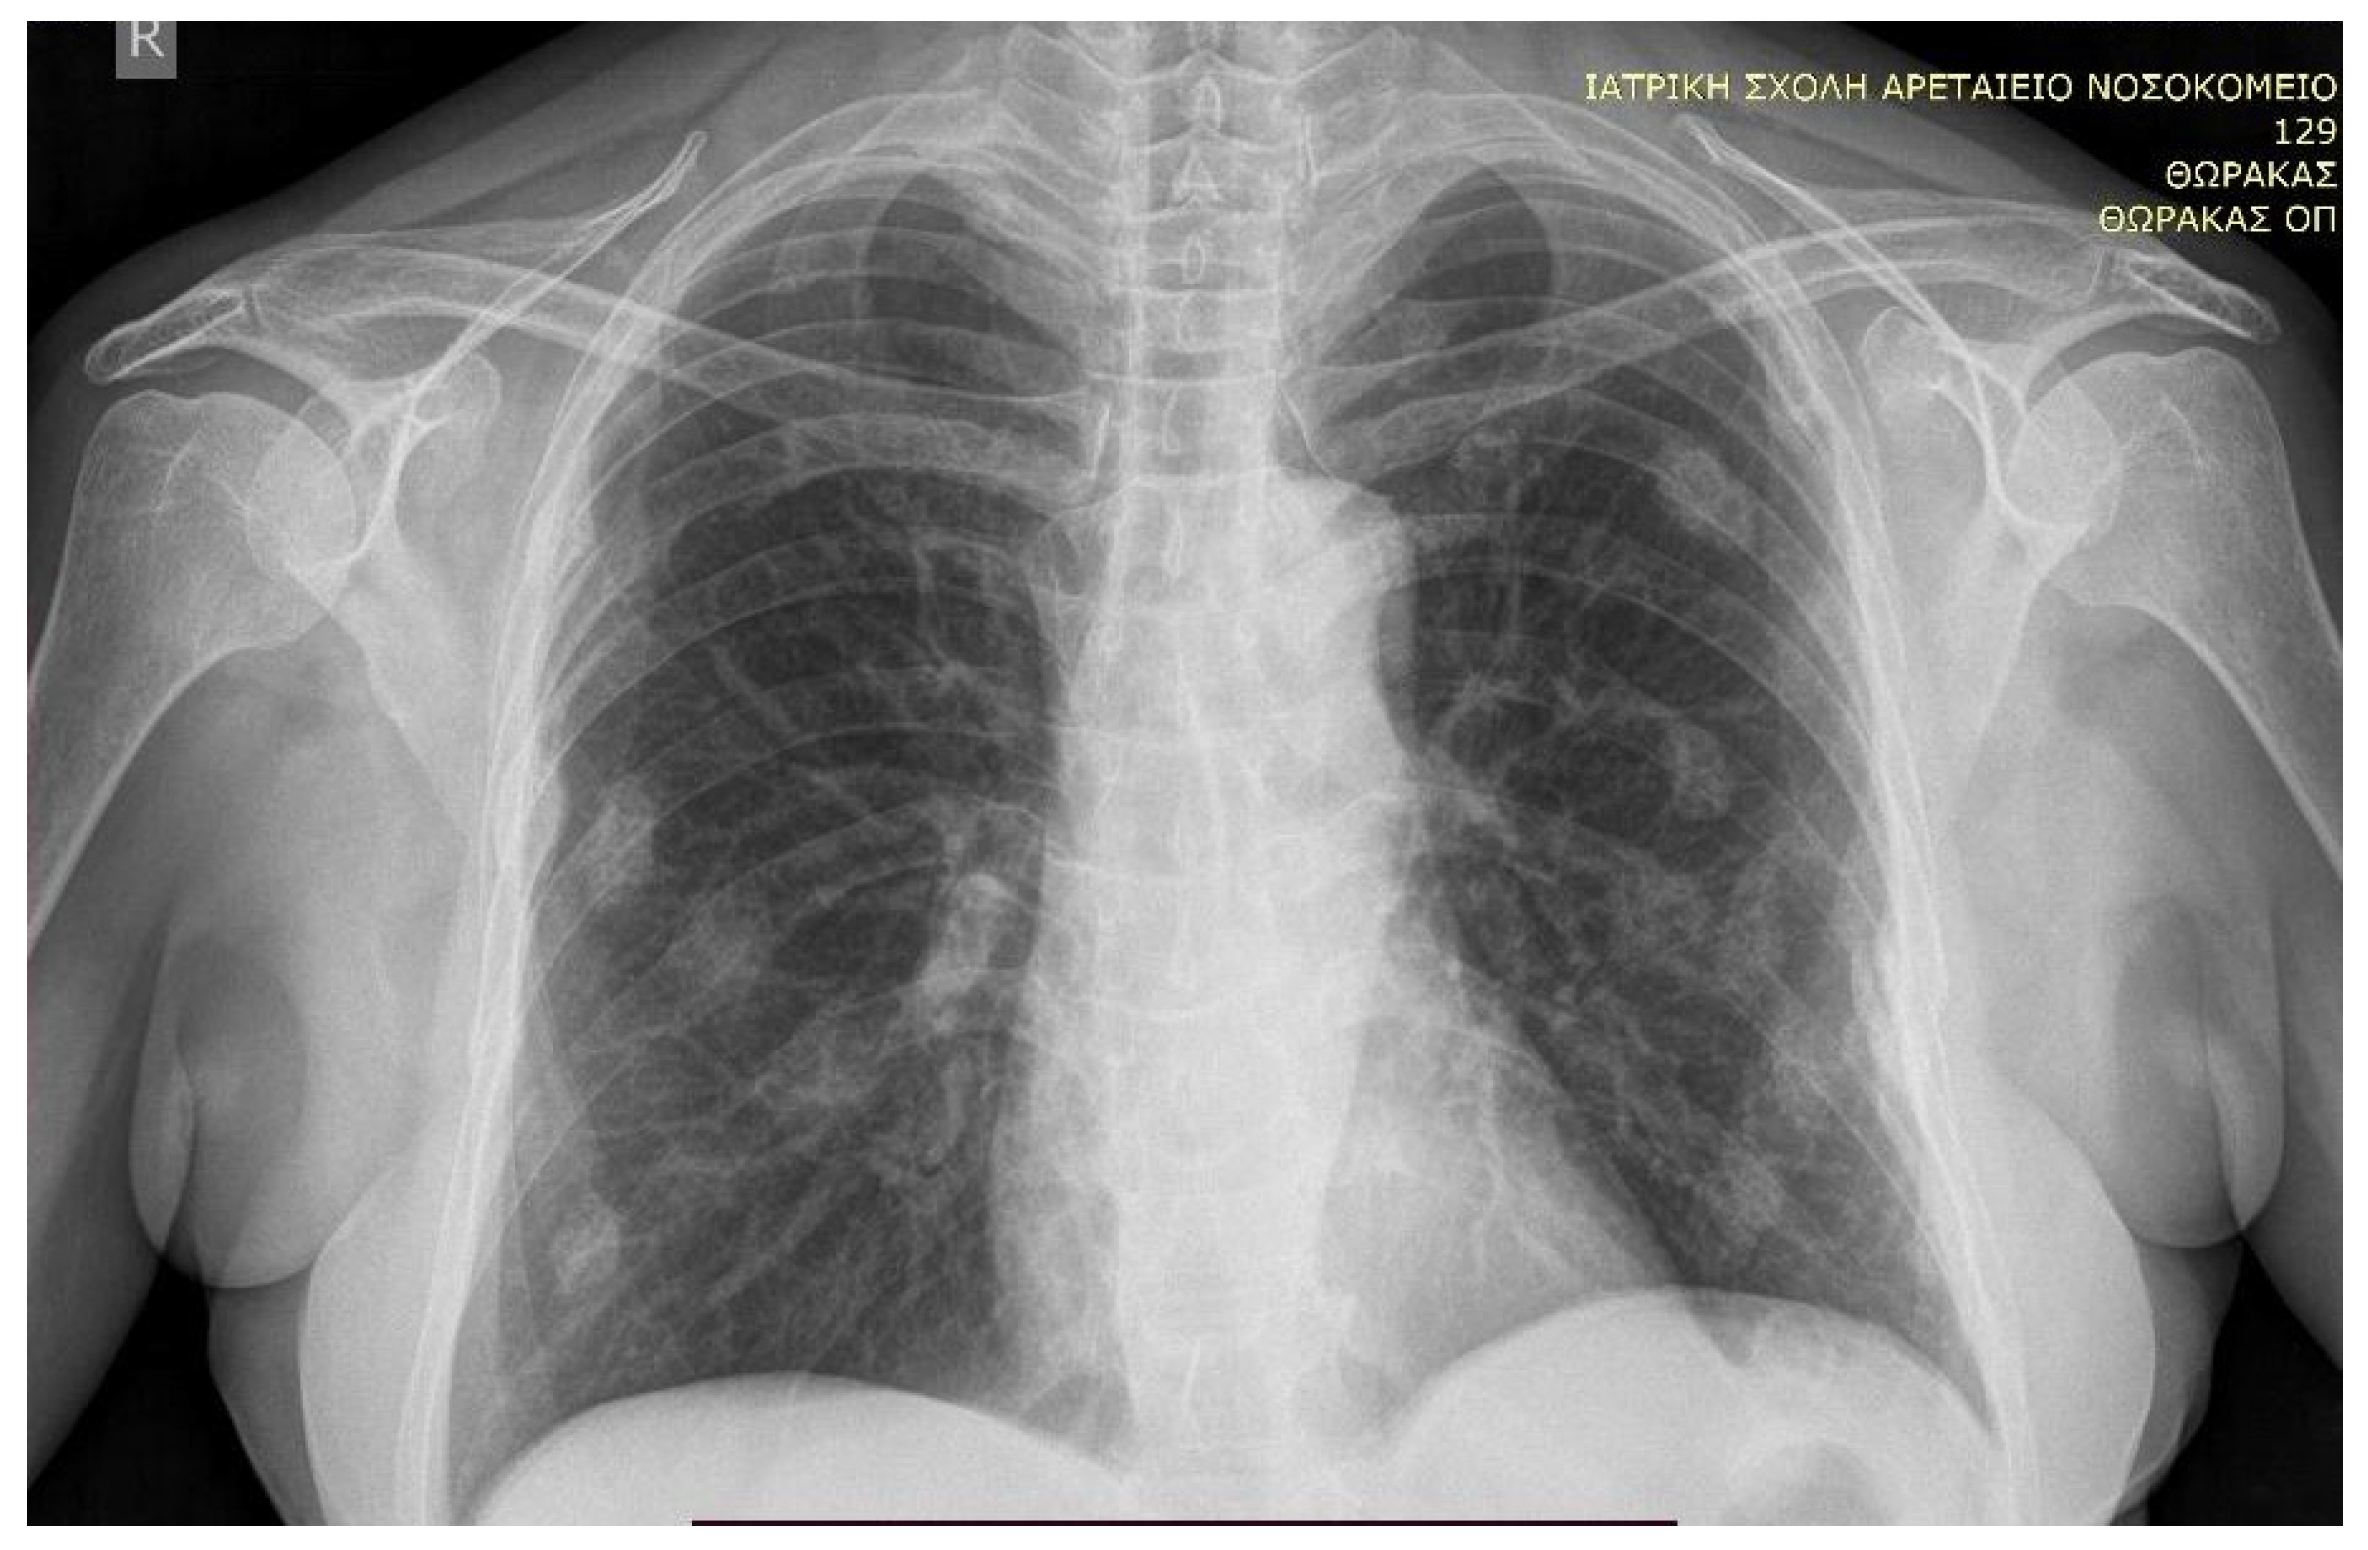

| Present case | Adrenal adenoma | 46 | F | sternum, middle phalanges of both indicators, rib, vertebral fractures T11, L1, sacrum | T-score lumbar −3.8 | Arterial Hypertension, Dyslipidemia, Diabetes | 395 μg/24 h | <2.4 pg/mL | 16.7 μg/dL (<1.8 μg/dL) |